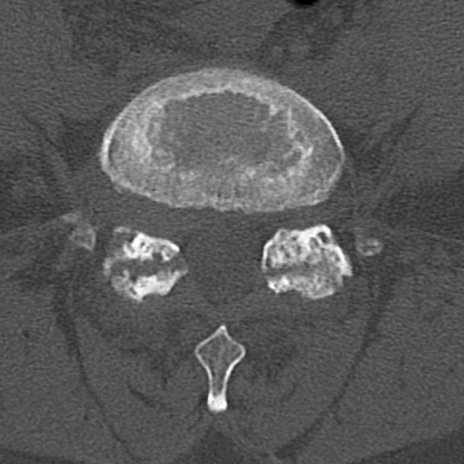

腰椎CT

横断像と矢状断像